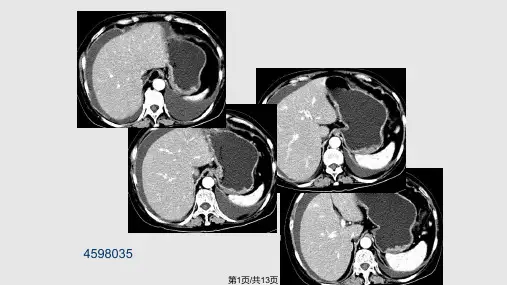

腹腔、腹膜后淋巴瘤

• 淋巴瘤大体病理切面呈鱼肉状, 发生坏死较少。显微镜下的小灶 坏死在CT 平扫或增强扫描时不易显示, 表现为均匀密度。

• 影像检查表现为腹腔、腹膜后均质的结节状肿块,包绕系膜血 管呈 “三明治”样表现,增强轻中度均匀强化。